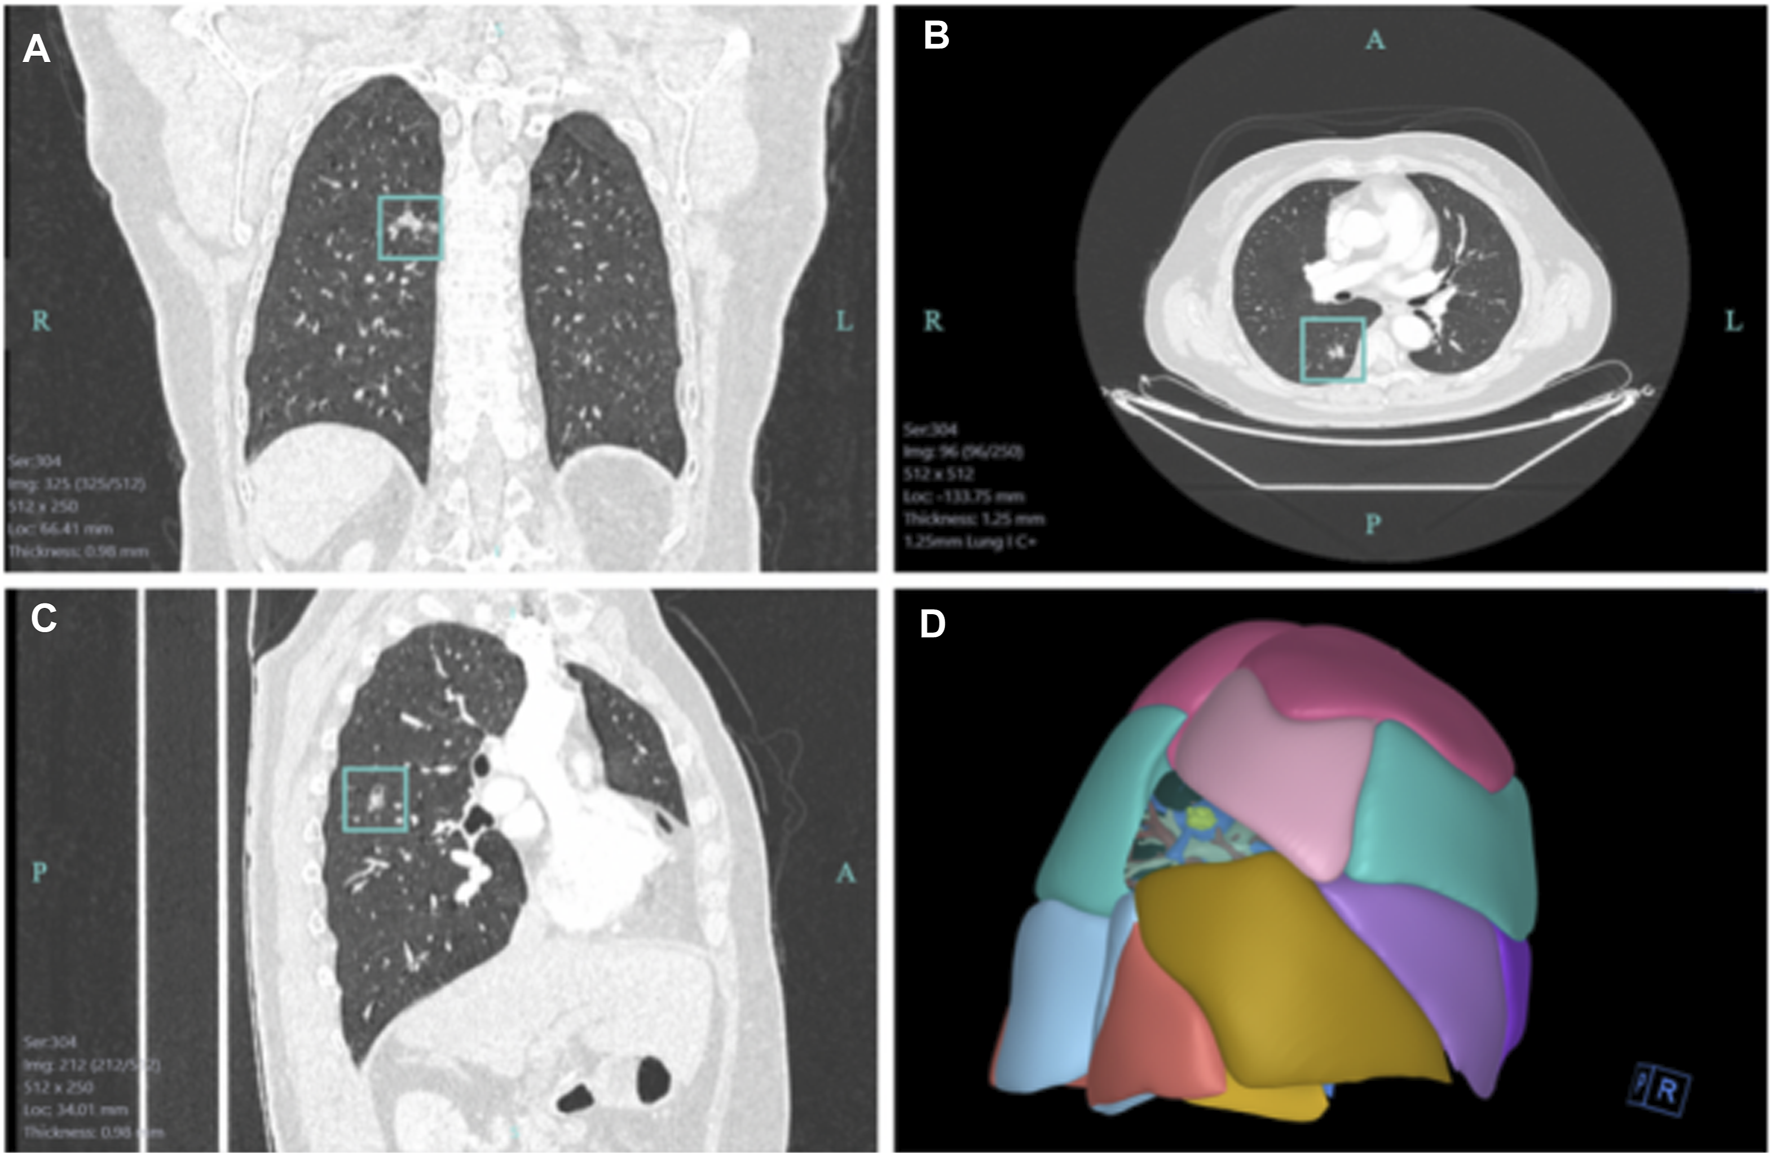

The metauniverse-based virtual 3D representation makes the surgery go on more smoothly than before. Volonté et al. (2013) reported the use of AR stereoscopic images of the Da Vinci robot for cholecystectomy. It has also been reported that AR technology provides doctors with a detailed view of important anatomy to guide the successful implementation of endoscopic radical prostatectomy (Chen et al., 2014; Mahmud et al., 2015). AR has been explored in the field of cardiac intervention, AR-based image analysis tools to measure the diameter and length of fluoroscopically identified vessel strictures might facilitate accurate stent selection for optimal treatment (Chen et al., 2014). AR can work with existing endoscopy set-ups makes clear the classification of polyps under gastroscope and improves the detection rate of adenomas (Mahmud et al., 2015). AR smart glasses have been confirmed with tactical advantages in prehospital triage in comparison with conventional approaches during mass casualty incidents (Wu and Ho, 2022). 3D reconstruction, a critical technology for establishing VR to express the objective world on a computer, has been employed in numerous subjects to reconstruct the two-dimensional (2D) CT image into a 3D image to display the lesion location and surrounding important tissues. For thoracic surgeons, 3D reconstruction holds significant clinical value for preoperative assessments regarding lesions and blood vessels (Figure 3). 3D reconstruction helps clinicians develop a more favorable operation plan of patients and increase operation safety (Jackson et al., 2003; Zhang and Liu, 2016; Song et al., 2021). Subsequently, using 3D printing technology, 3D images can be converted into solid objects that are currently applied in orthopedics, congenital heart disease, and thoracic surgery for the chest wall reconstruction and achieved good curative effect and functional reconstruction (Smelt et al., 2020; Wu et al., 2021). With the progress of science and technology, 1 day, the preoperative surgeon can perform surgical operation repeatedly before realistic surgery on the 3D image, such that the actual scene of the lesion can be completely reproduced in metaverse.

FIGURE 3

The 3D reconstruction image based on the 2D CT image in the First Hospital of Jilin University. (A) Coronal view of a 2D CT lesion. (B) Transverse view of a 2D CT lesion. (C) Sagittal view of a 2D CT lesion. (D) Three-dimensional reconstruction image based on the 2D CT lesion.